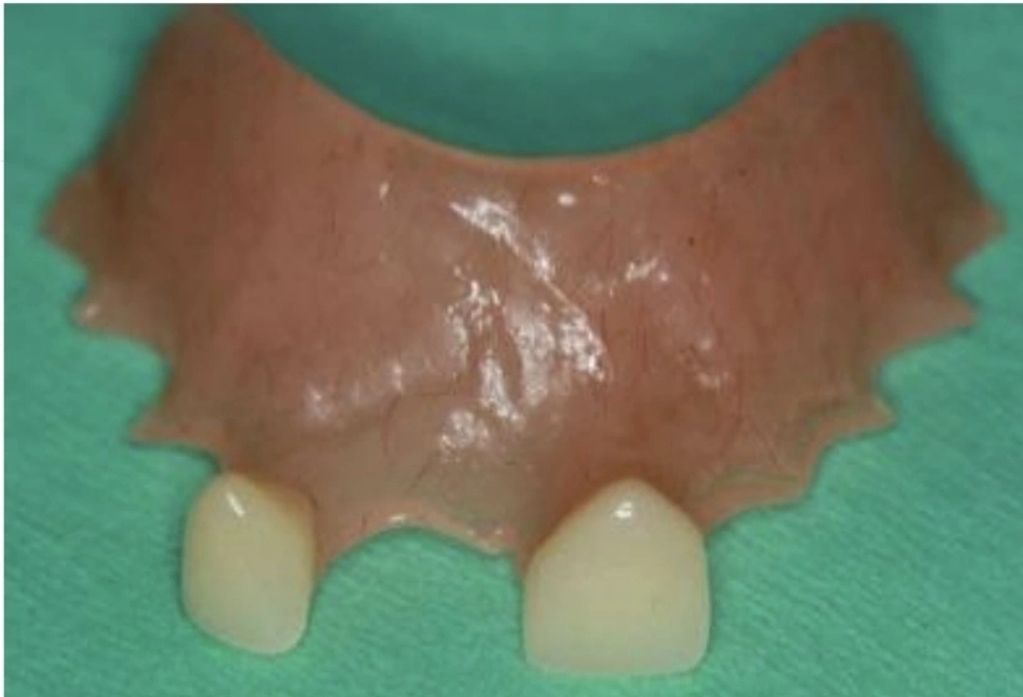

Observamos la prótesis removible que usaba el paciente antes del procedimiento, la cual tallaba, se movía y era bastante incomoda para el paciente.